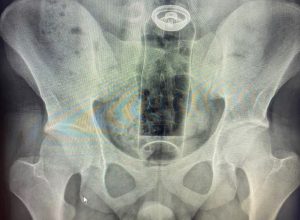

Uma “brincadeira” íntima terminou em caso de emergência médica para um jovem de 19 anos, que precisou ser internado para retirar um frasco de desodorante que fi...